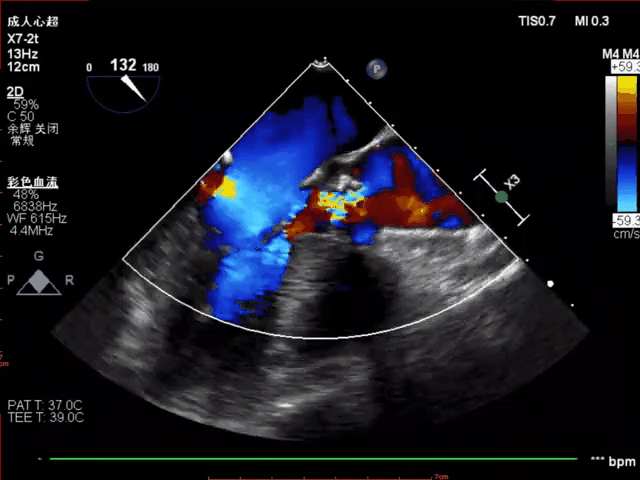

植入后超声评估:

超声评估血流动力学改善明显